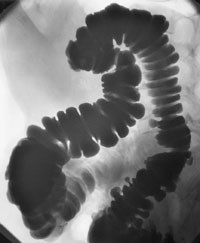

Samlet sett bør man være tilbakeholden med medikamentell behandling ved irritabel tarm-syndrom. Volumøkende laksantia ”normaliserer” avføringen både ved diaré og obstipasjon (3) og kan forsøkes. Man regner med at motilitetsforstyrrelse er viktig i patogenesen (fig 1) (4). Imidlertid er effekten av medikamenter som påvirker motilitet dårlig dokumentert. Det bør mane til forsiktighet at cisaprid, et såkalt prokinetikum som virker via en serotoninreseptor og fører til økt frigjøring av acetylkolin fra nerveceller (5), etter mange års bruk nå har vist seg å kunne ha letale bivirkninger (6). Tatt i betraktning at disse medikamentene i beste fall har en marginal effekt, tilsier dette at man skal være forsiktig ved bruk av slike medikamenter ved irritabel tarm-syndrom.